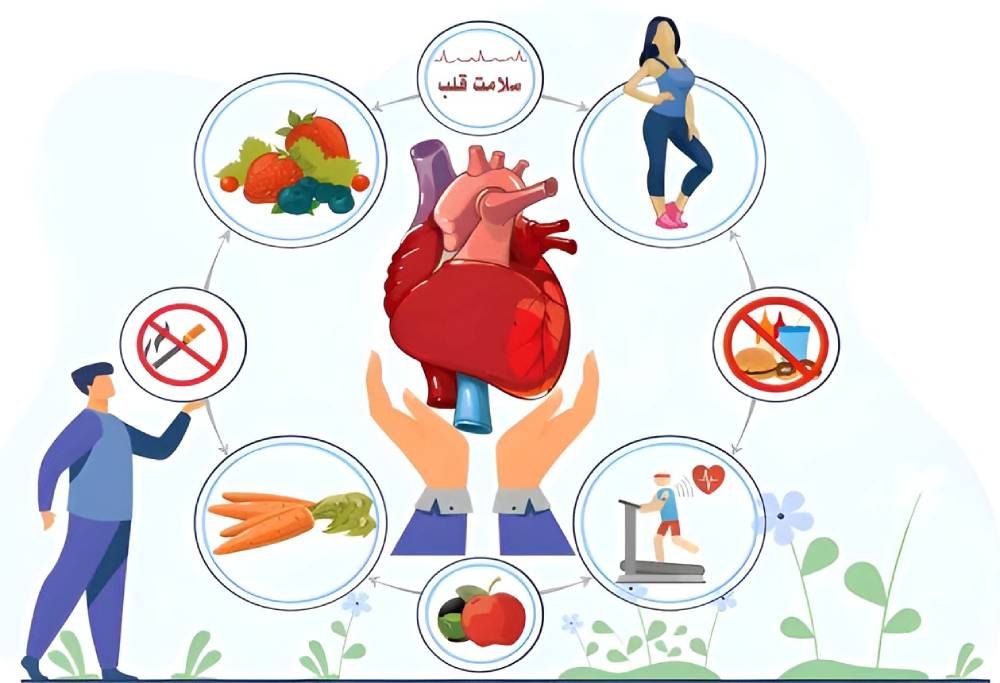

- تغذیۀ ناسالم: تغذیۀ سرشار از مواد قندی، چربیهای حیوانی، غذاهای فرآوریشده، چربیهای ترانس و نمک افزایش احتمال سکتۀ قلبی را به دنبال دارد. پس میوه، سبزی، فیبر و روغنهای سالم را به میزان فراوان در برنامۀ غذاییتان بگنجانید.

- به اندازۀ کافی ورزش نکردن: ورزش نکردن و کمتحرکی خطر سکته قلبی را افزایش میدهد. ورزش منظم سلامت قلب را ارتقا میدهد.

- کشیدن سیگار: کشیدن سیگار یا تماس بلندمدت با دود سیگار دیگران یکی از عاملهای خطر سکته قلبی است. پس اگر سیگاری هستید، سیگار را ترک کنید.